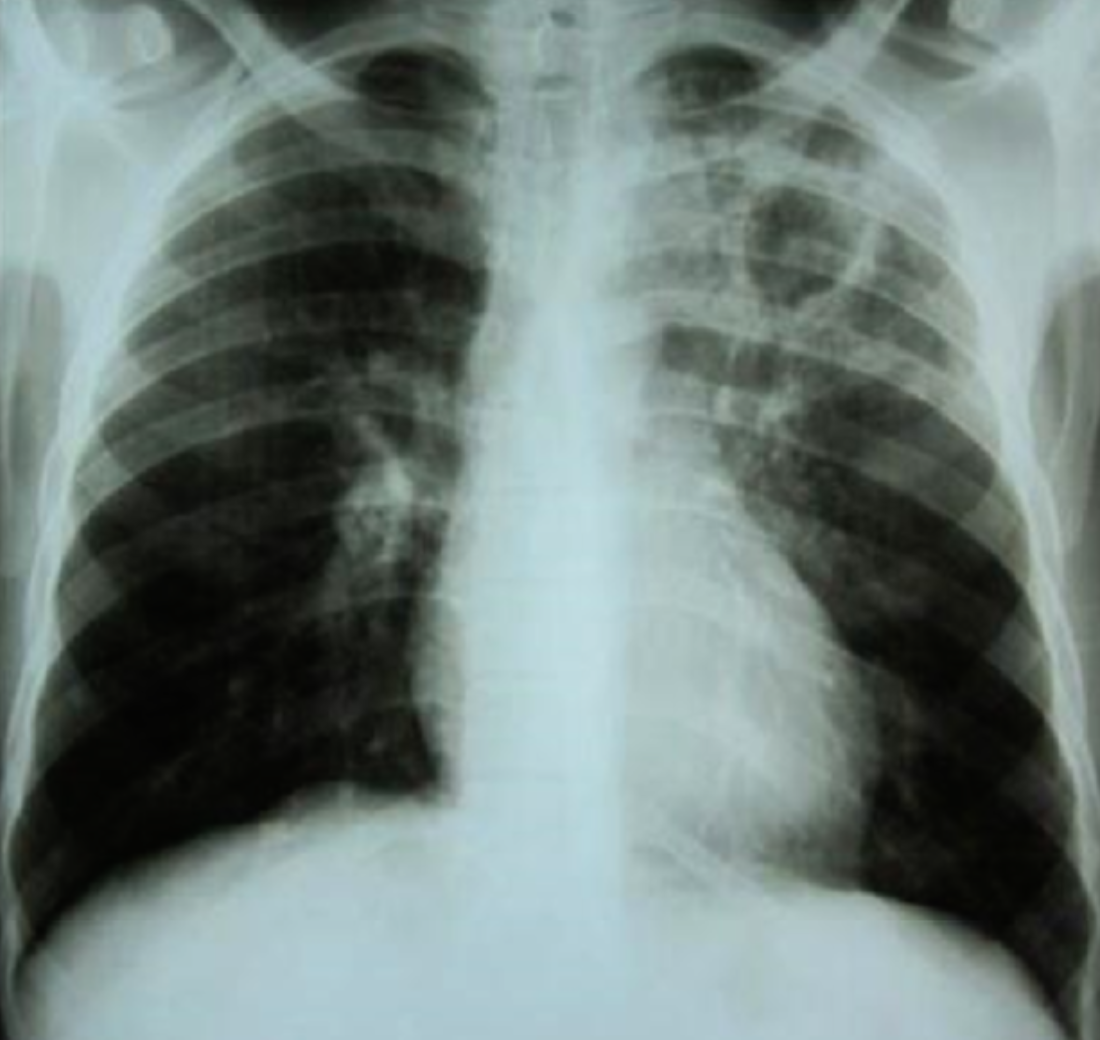

32 year female presented with fever & weight loss

Describe radiological findings

What’s the abnormal here? You should read the whole chest film PA VIEW:

- The trachea looks central.

- Heart looks normal in shape and size.

- What’s abnormal? You have all this reticular shadows and nodules all over the lungs,

Bronchitis does not give a picture like this while miliary TB is a possibility.

differential diagnosis of miliary shadow of the lung?

1- Miliary TB

2- Sarcoid

3- Diffuse metastatic lesions.

4- Lymphomas

5- Silicosis